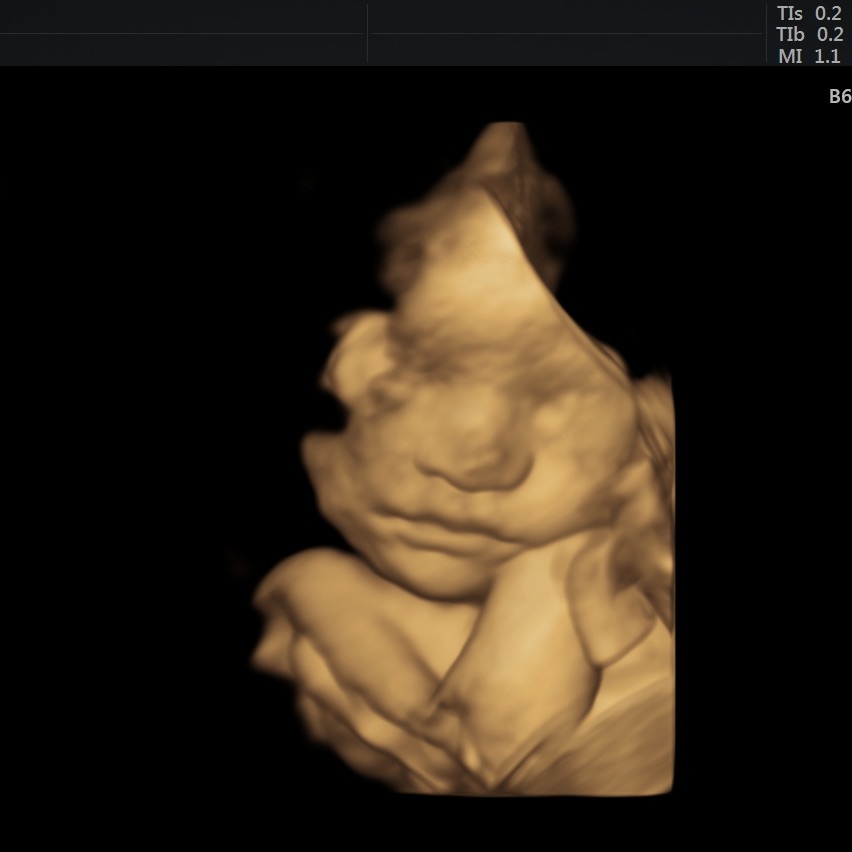

Ultrasound after Spotting Scare

I mentioned a spotting scare in my last pregnancy diary post, and I’m happy to share that I haven’t had any spotting since then! I had an ultrasound about a week after the incident and it was reassuring to hear that everything looked normal. Seeing baby boy was awesome, too!